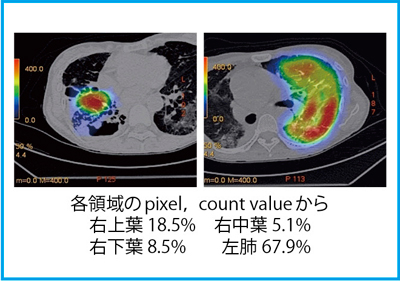

核医学(RI検査)(医療関係者の方向け) | 京都市立病院, 第52回日本核医学会学術総会/第32回日本核医学技術学会総会学術,

第52回日本核医学会学術総会/第32回日本核医学技術学会総会学術, 第52回日本核医学会学術総会/第32回日本核医学技術学会総会学術,

第52回日本核医学会学術総会/第32回日本核医学技術学会総会学術, 進行性線維化を伴うCTD-ILD診療における急性増悪予防の重要性,